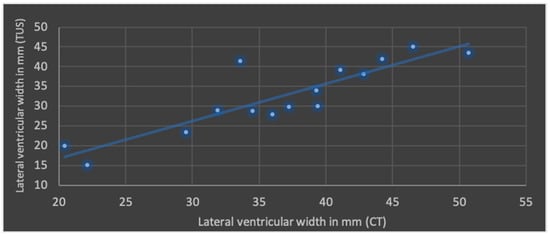

The Pearson’s correlation coefficient (r), including mean values and standard deviation of both modalities in terms of ML shift, lateral ventricular width, subdural space and ICH is shown in Figure 4, Figure 5, Figure 6 and Figure 7.

Figure 5.

Correlation of transcranial ultrasound (TUS) and computed tomography (CT) in terms of lateral ventricular width (r = 0.88; p < 0.001; mean value TUS: 32.5 ± 9.0 mm; mean value CT: 36.6 ± 8.4 mm).

The best correlation represented by Pearson’s correlation coefficient was shown in ML shift and lateral ventricular width. The evaluation of ICHs in TUS revealed a slightly weaker correlation, but with a p-value below 0.05, still indicating significance at the standard level. No significant correlation was found in terms of subdural space between both modalities; mean values obtained through CT were higher than those in TUS.

Regarding the application of TUS in post-craniectomy patients, the literature predominantly consists of case studies and studies with small patient cohorts [,,,]. Only a few studies compare CT and TUS in terms of visualizing relevant structures, and they are mostly obtained through the temporal acoustic window in non-craniectomized patients [,,,]. In a recently published prospective pilot study by Chouhan et al., 40 post-hemicraniectomy patients were examined. A strong correlation between both imaging modalities was observed in terms of ventricular width. However, a high standard deviation for ultrasound measurements was noted in a few patients with a severely enlarged ventricular system. Identification of hyperechoic lesions was described as more effective than hypoechoic ones. A correlation of lesion size (diameter or volume) was not performed. The working group describes the curved transducer as the most useful for this purpose. This corresponds with our study, where a curved probe was also selected []. In an older study by Bendella et al., 102 patients were examined using TUS. Ultrasound was performed no later than 24 h after cranial CT, which corresponds with our time frame. A strong correlation was found for ventricular diameters and ML shift. In this analysis, as in our study, the Pearson correlation coefficient was determined. Regarding lateral ventricular width and ML shift, slightly higher coefficients were observed here, although both study results are statistically significant. It cannot be ruled out that the prospective design and standardized study protocol as well as the larger patient number contributed to this outcome. TUS examinations were performed by three experienced investigators, analogous to our study. A qualitative assessment of the examiner subgroups was not conducted [].

Transcranial ultrasound is a safe, cost-effective, and time-efficient method that may become increasingly relevant for imaging post-hemicraniectomy patients. In our experience, transcranial ultrasound was effective in visualizing intraventricular catheter placement, the ventricular system, midline and space-occupying lesions. The present study showed a strong correlation in terms of midline shift, lateral ventricular width and intracerebral hematomas between computed tomography and transcranial ultrasound. Further enhancements in image quality could potentially reduce the overall need for CT scans.